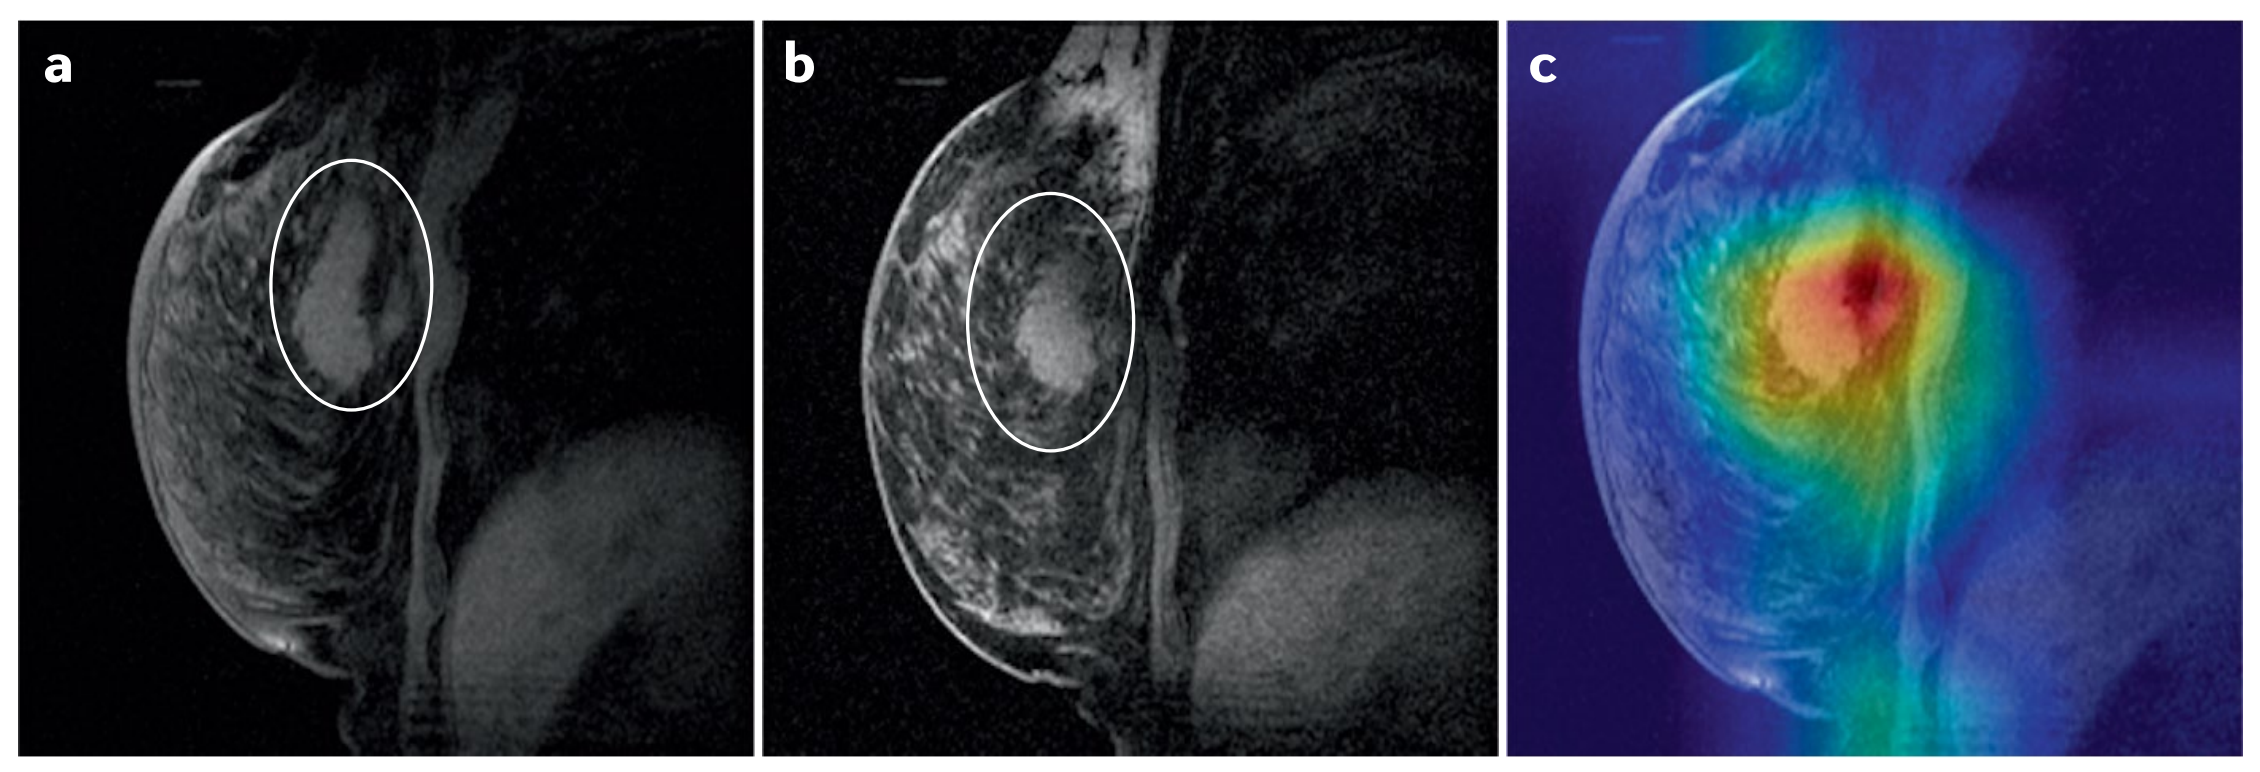

对于黑盒模型,比解释性更简单的是可解释性。例如,类别激活图(CAMs)【142】(图6)显示了模型做出决策时图像中最重要的部分。

图 6 展示了类激活映射(Class Activation Mapping, CAM)的概念,这是一种用于解释深度学习模型(尤其是卷积神经网络, CNNs)决策过程的方法。CAM 通过可视化模型在做出预测时认为图像中哪些区域是最重要的来提供模型的可解释性。这对于医学图像分析尤其有用,因为医生和研究人员可以更好地理解模型是如何根据图像特征做出诊断的。

在图 6 中,展示了以下几个关键点:

-

图像区域的重要性:

- CAM 通过为图像中的每个区域分配一个重要性分数来工作,这些分数表明了每个区域对于模型输出的贡献程度。

- 分数较高的区域意味着对于模型做出特定类别预测更为重要。

-

可视化:

- CAM 通常通过在原始图像上叠加一个热图(heatmap)来可视化,其中颜色的变化(如从蓝色到红色)表示区域的重要性或“激活度”。

- 颜色越暖,表示该区域对于模型的决策越重要。

-

模型决策的解释:

- 通过 CAM,可以识别出模型在做出决策时所关注的图像特征,例如肿瘤的特定形状、大小或纹理。

- 这可以帮助医生理解模型的行为,判断模型是否关注了与医学知识相符的图像特征。

-

图像示例:

- 图 6 包括几个图像示例,展示了在接受

新辅助化疗前后的乳腺 MRI 图像,以及对应的 CAM 图像。 - 在 CAM 图像中,模型预测对化疗有反应的区域会被突出显示,这可以为临床决策提供支持。

- 图 6 包括几个图像示例,展示了在接受

-

临床应用:

- CAM 可以帮助建立医生对 AI 模型的信任,通过提供模型决策背后的直观证据。

- 此外,它还可以揭示模型可能依赖的不相关特征,这对于模型的改进和避免潜在的误诊非常重要。

总体而言,图 6 强调了在医疗影像分析中解释模型决策的重要性,并且 CAM 是实现这一目标的有效工具之一。通过这种可视化技术,可以提高模型的透明度,增强医疗专业人员对 AI 系统的信任,并可能指导更精确的临床决策。